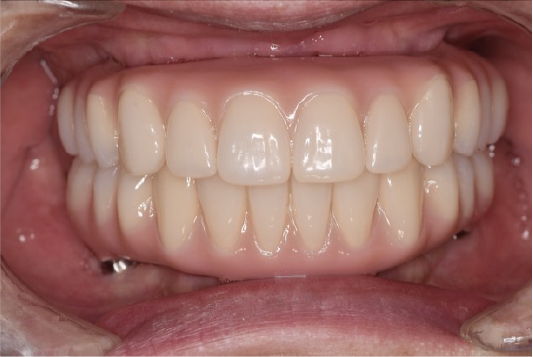

CASE01

■ 治療内容

上下顎All-on-4インプラント治療

■ 治療費用

7,438,000円(税込)

■ 治療期間

約10ヶ月

■ リスク

治療後の腫れや出血、またメンテナンスを怠ることで周囲炎のリスクあります。